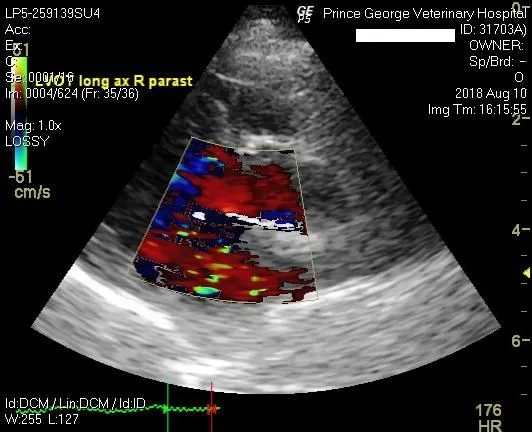

Echocardiography uses ultrasound to obtain images of the heart. This way we can not only assess the size of the heart and its various chambers, but also evaluate the heart muscle, the function of the heart muscle and the condition of the valves in the heart.

Using something called 'Doppler' we can also assess the pattern of blood flow and the speed of blood flow throug the various valves in the heart.

Echocardiography is a very important tool in diagnosing conditions like cardiomyopathy (heart muscle disease), chronic valvular disease or pericardial effusion (heart sac filling up with liquid).